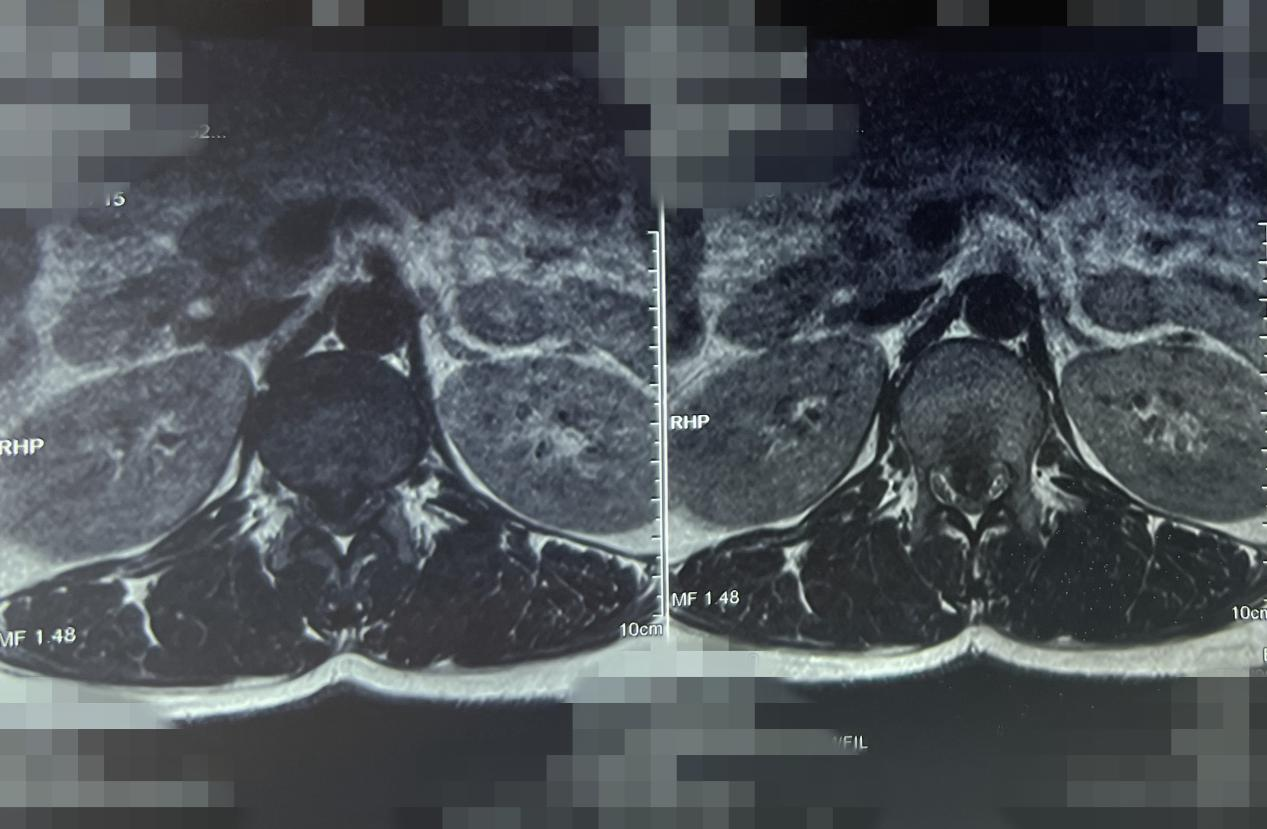

杨俊松副主任医师接诊后结合患者病史、体征和影像学资料指出,患者胸12 腰1椎间盘突出症诊断明确,双侧脊髓神经严重受压,椎间盘严重钙化。

MRI显示:间盘突出&脊髓神经严重受压